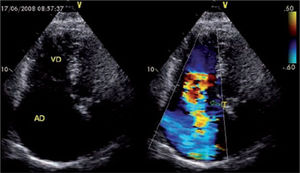

El diagnóstico de IT y la decisión de intervenir debe ser hecho an- tes de la cirugía, ya que la severidad de la IT está influenciada por las condiciones intraoperatorias incluyendo los efectos de la anes- tesia. Si bien, la ecografía trans-esofágica (ETE) intraoperatoria es esencial en la determinación de la disfunción valvular mitral y aórtica, ésta puede subestimar la severidad de la IT y llevar a deci- siones incorrectas42. Por este motivo, la tendencia actual es indicar anuloplastía en casos de dilatación anular (>40mm or >21mm/m2 en la visión de 4 cámaras). La Fig. 4 muestra una insuficiencia tricuspídea severa mediante imagen ecocardiográfica43.